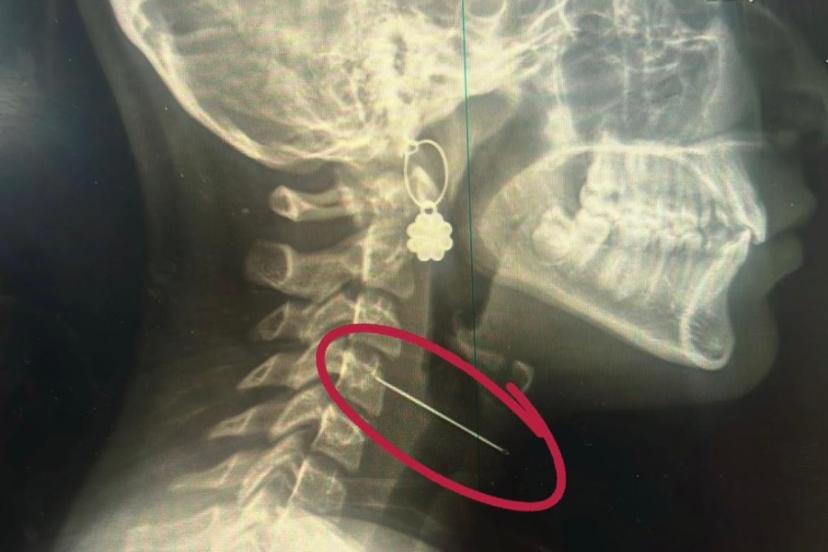

Çocuklarda sık karşılaşılan risklere değinen Özkaya "Günlük hayatta çocuklarda sık karşılaşılan yabancı cisim yutulması, kimyasal madde içilmesi ve solunum yollarına yabancı cisim kaçması önemli sağlık sorunları arasında yer almaktadır. Özellikle ilk üç yaşındaki çocuklar, yerde buldukları nesneleri ağızlarına götürme eğilimindedir. Madeni paralar, disk piller, iğneler ve küçük oyuncak parçaları çocuklar tarafından yutulabilmekte; bu maddeler yemek borusuna ya da solunum yollarına kaçabilmektedir. Bu tür durumlarda ailelerin olaya şahit olmaları hâlinde çocuğun ağzını kontrol etmeleri, yutma şüphesi varsa vakit kaybetmeden en yakın sağlık kuruluşuna başvurmaları gerekmektedir." dedi.